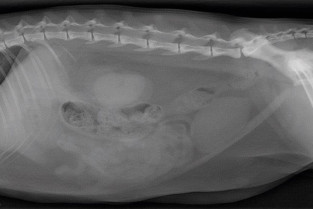

• adopter une méthodologie pour interpréter les affections de la cavité péritonéale et rétropéritonéale chez les carnivores domestiques ;

• décrire l’aspect normal et anormal des organes péritonéaux et rétropéritonéaux chez les carnivores domestiques ;

• détecter une obstruction digestive.

TD de lecture de radiographies numériques